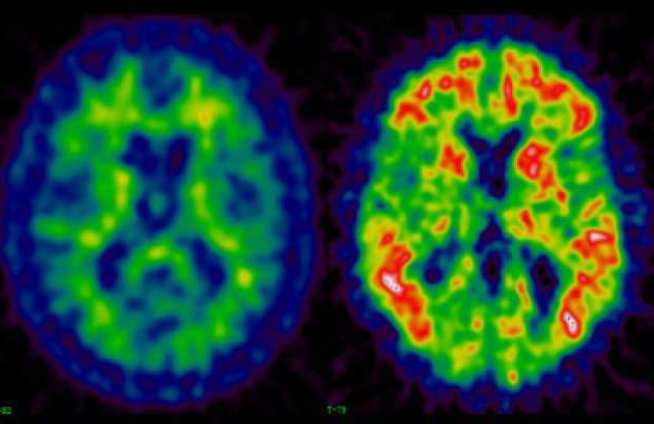

Alzheimer’s disease is a progressive neurodegenerative disease characterised by extracellular β-amyloid plaques and intracellular neurofibrillary tangles. In AD brain, it has been suggested that the accumulation of the amyloid-β peptide (Aβ) might responsible to develop the AD, which might due to overproduction of Aβ and/or the failure of clearance mechanisms.